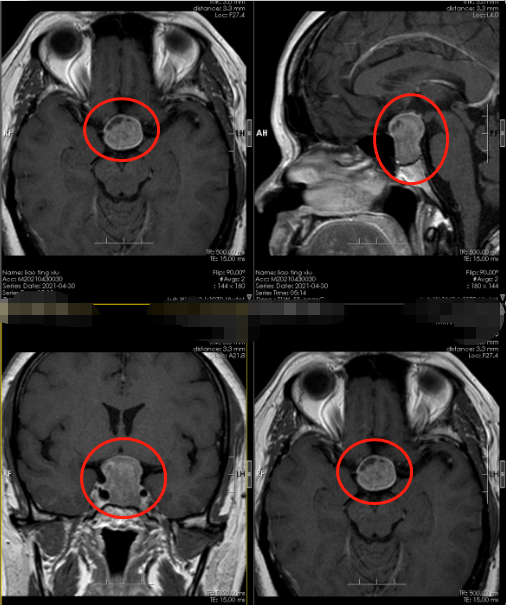

廖阿姨入院后很快就安排了检查,其神经系统查体未见明显定位体征;我院颅脑MR垂体平扫+增强示::鞍区及鞍上区病变,考虑垂体大腺瘤合并囊变(Knosp2级,颈椎腰椎MR提示可见椎间盘突出改变,考虑其肢体麻木与颈腰椎病有关。其头晕头痛为鞍占位区病变所致。

明确诊断后廖阿姨由内科转至神经外十科治疗,5月10号廖阿姨在全麻下行“神经内镜下经鼻蝶入路鞍区垂体瘤切除术”,术中磨除鞍底骨窗约1.5cm大小。钩刀“+”字型切开硬脑膜,见肿瘤灰白色,质硬,正常垂体组织位于右后方,予以保留,全切肿瘤,双侧海绵窦内侧壁无肿瘤残留,无明显脑脊液漏,术腔内留置明胶海绵片,检查无明显出血。术后安返监护室,给予止血、护胃、营养神经等对症和支持治疗。手术过程很顺利,肿瘤全切。